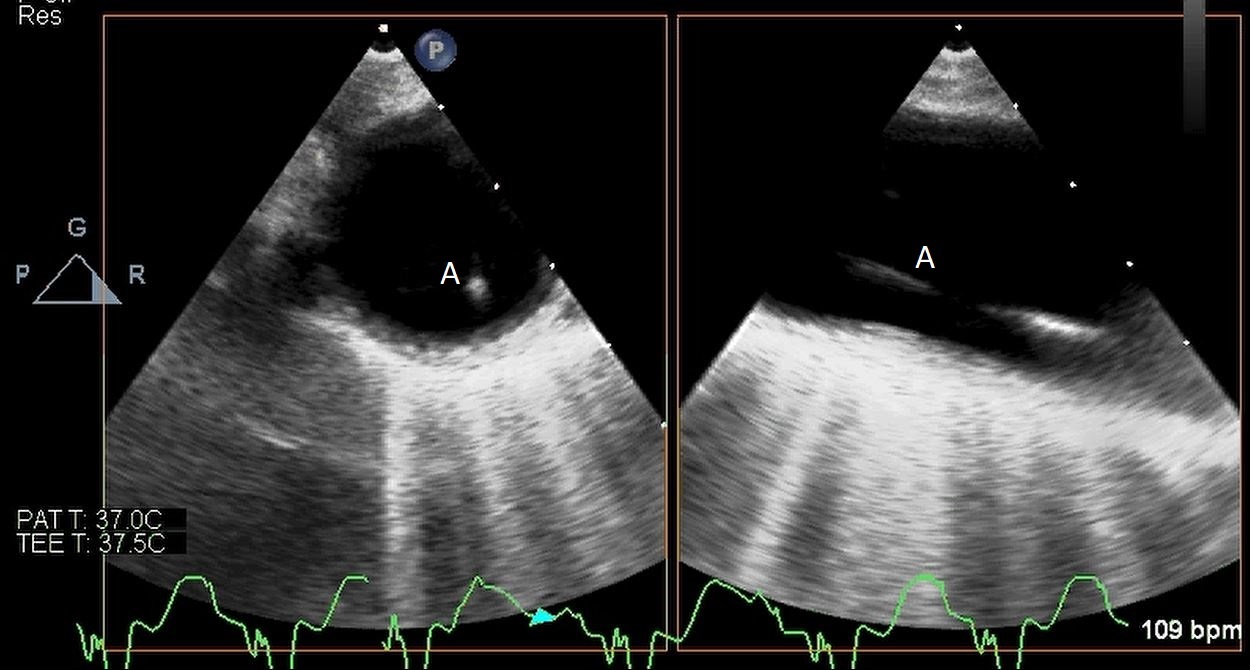

The intra-aortic balloon pump is a percutaneously placed counter pulsation device which helps in decreasing afterload as well as augmenting coronary perfusion. Initially developed in the 1960s it is the oldest MCS device and given its simplicity, cost effectiveness, and ease to implant and explant, it is the most commonly used temporary support device [6]. Although it is typically placed in the cardiac catheterization lab under fluoroscopic guidance, TEE can be utilized to help in its placement in the intubated patient in the intra-operative setting. The femoral artery is the most common site of placement however they can on occasion be placed in alternative sites such as the axillary artery or directly into the aorta [7, 8]. When placed via the femoral artery, it is threaded over a guidewire. TEE can be used to visualize both the guidewire as well as the tip of the IABP catheter during placement (Fig. 1) [9]. Ideal positioning of the balloon tip is 1–2 cm distal to the left subclavian artery to derive maximal hemodynamic benefit [10]. Positioning can be confirmed by visualizing the descending aorta and then withdrawing the TEE probe until the left subclavian artery and aortic arch are visualized. Upon activation of the balloon pump the gas filled balloon will cause shadowing and reverberation artifacts (Fig. 2). Its presence can be used as confirmation of proper function of the device. If these artifacts are not seen or bubbles are visualized in the aorta, rupture of the IABP should be suspected [9]. In addition to hemodynamic monitoring with a Swan-Ganz catheter, TTE can be used to monitor LV function after IABP placement and can help guide weaning of IABP support. It can also visualize any new or worsening aortic regurgitation. Given that IABPs work by reducing afterload, on rare occasions they can precipitate dynamic outflow tract obstruction and paradoxically worsen cardiogenic shock. Examples include patients with a relatively preserved basal or septal myocardial function in scenarios such as takotsubo cardiomyopathy or acute myocardial infarctions. Doppler imaging and color flow doppler can be used to identify such scenarios [11].

Fig. 1.TEE demonstrating IABP in descending aorta (A).

TEE demonstrating IABP in descending aorta (A) with reverberation artifact seen behind it upon activation (B).